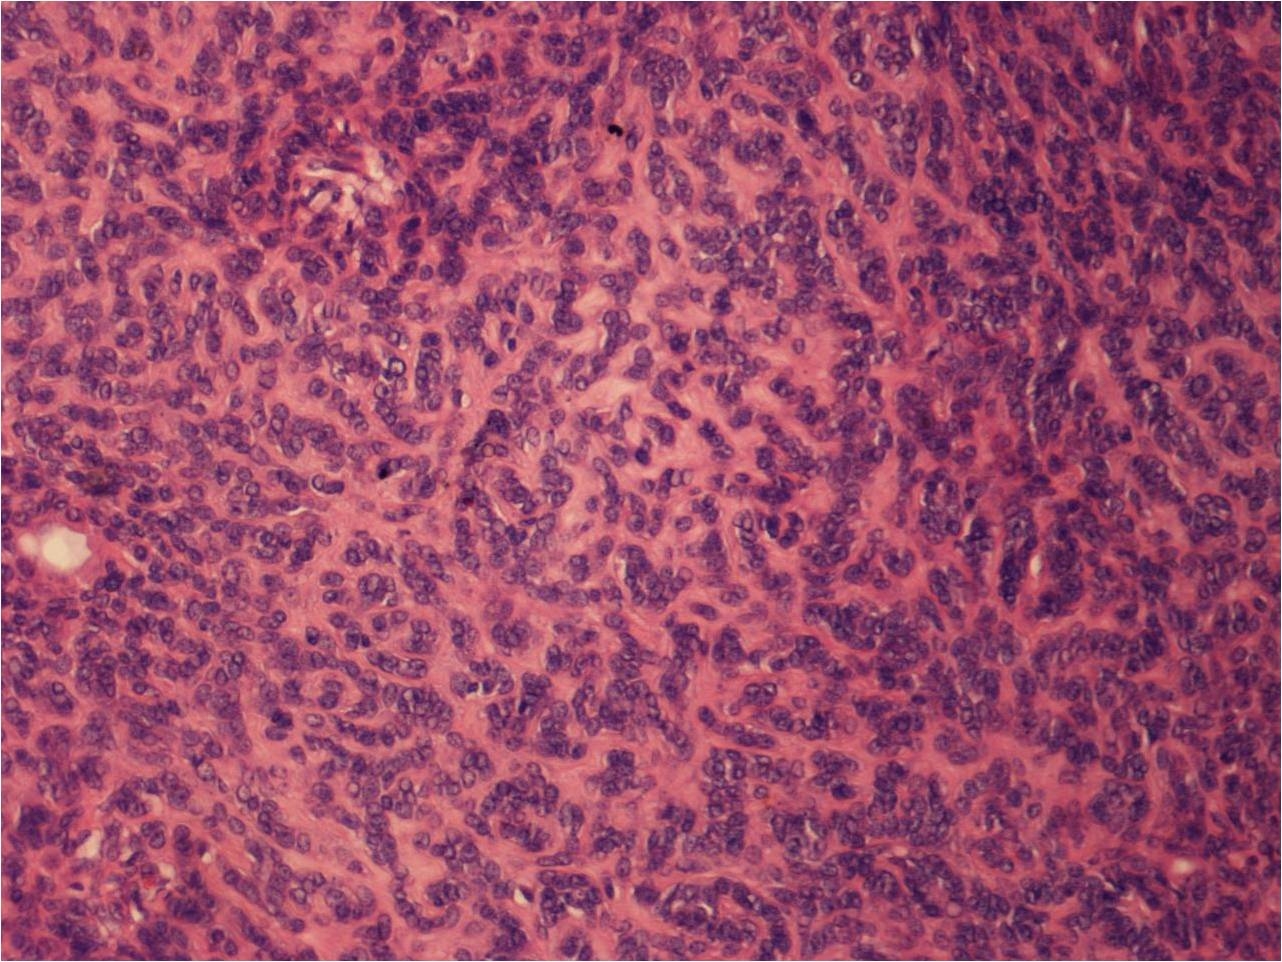

Lesion from the flank of a 46 year old male.

Contributor: Dr Ravi Suchak